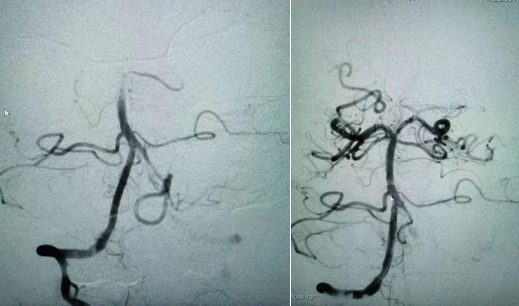

黃先生今年36歲,清晨起來鍛煉時突發(fā)頭暈伴肢體乏力被送到惠州三院急診搶救室。到了醫(yī)院后,患者已經(jīng)言語含糊不清,被診斷為急性腦梗死、基地動脈閉塞!惠州三院神經(jīng)醫(yī)學(xué)中心卒中救治團隊立即為他開通腦卒中綠色通道,經(jīng)過“動脈取栓”治療后,患者才重獲健康,恢復(fù)良好。

左為術(shù)前血管造影、右為術(shù)后開通血管造影